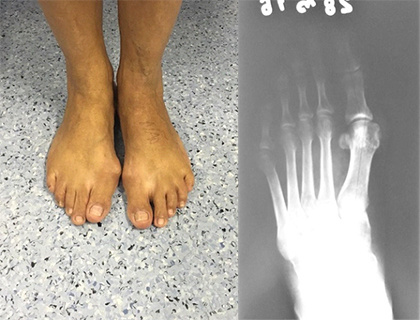

A Cirurgia Percutânea do Pé é um procedimento cirúrgico minimamente invasivo que fazemos por meio de pequenas incisões na pele. Frequentemente, médicos a utilizam para tratar diversas condições do pé, como joanete (hálux valgo), dedos em garra ou martelo, hálux rígido, calosidades e fascite plantar.

Realizamos a cirurgia percutânea com incisões de 2-3 mm, usando instrumentos específicos e fluoroscopia para guiar o procedimento. Dessa forma, essa técnica permite corrigir problemas como joanetes (hálux valgo), deformidades dos dedos menores (dedo em martelo, dedo em garra), metatarsalgias e esporão de calcâneo. Em resumo, as vantagens incluem menor cicatriz, menor inchaço, redução da dor no pós-operatório e um tempo de recuperação mais curto em comparação com as técnicas cirúrgicas tradicionais. Portanto, essa é uma excelente opção para quem busca um procedimento menos agressivo.